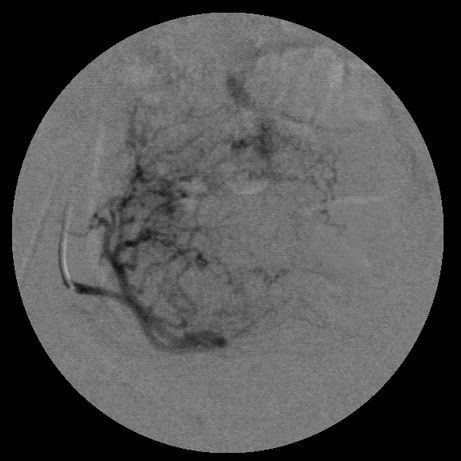

女,35岁,子宫多发肌瘤

栓塞剂用的是进口pva,二瓶,几千块呀,栓塞面积应该不大吧,呵呵

以后会有代偿血管生成的

要超选到子宫动脉上支吗?